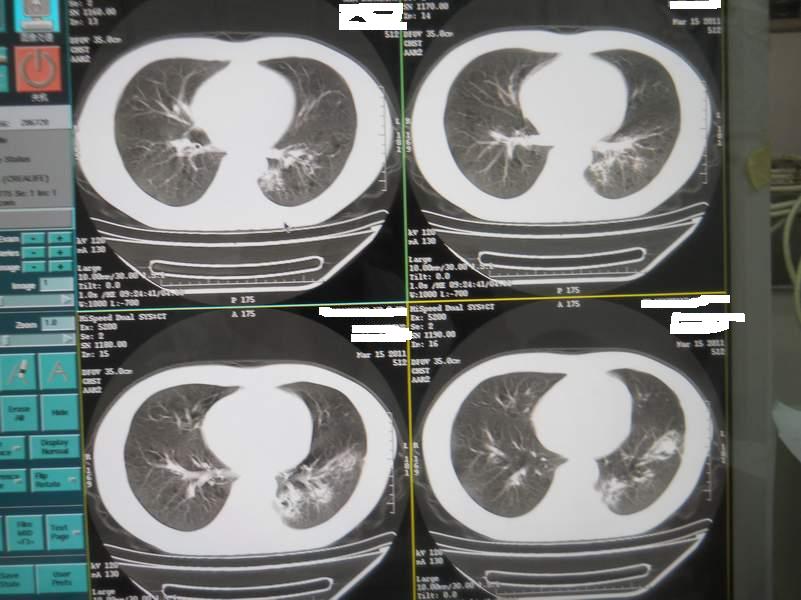

肺霉菌感染

男,22岁,一年前诊断马尔菲尼青霉菌感染,多次复查CT。多次HIV阴性。最近两次CT图片。有实验室结果。

最近实验室检查结果:霉菌感染。